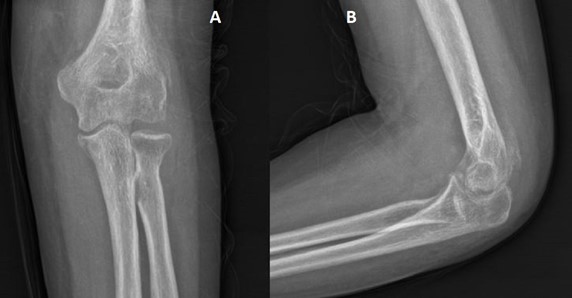

An X-ray of the elbow with AP and lateral views as shown in Figure 5 revealed a posterolateral dislocation of the elbow. The patient was hospitalised and pre-operative bloodwork was done in preparation for a surgical reduction.

Figure 5: Posterolateral dislocation of the elbow joint